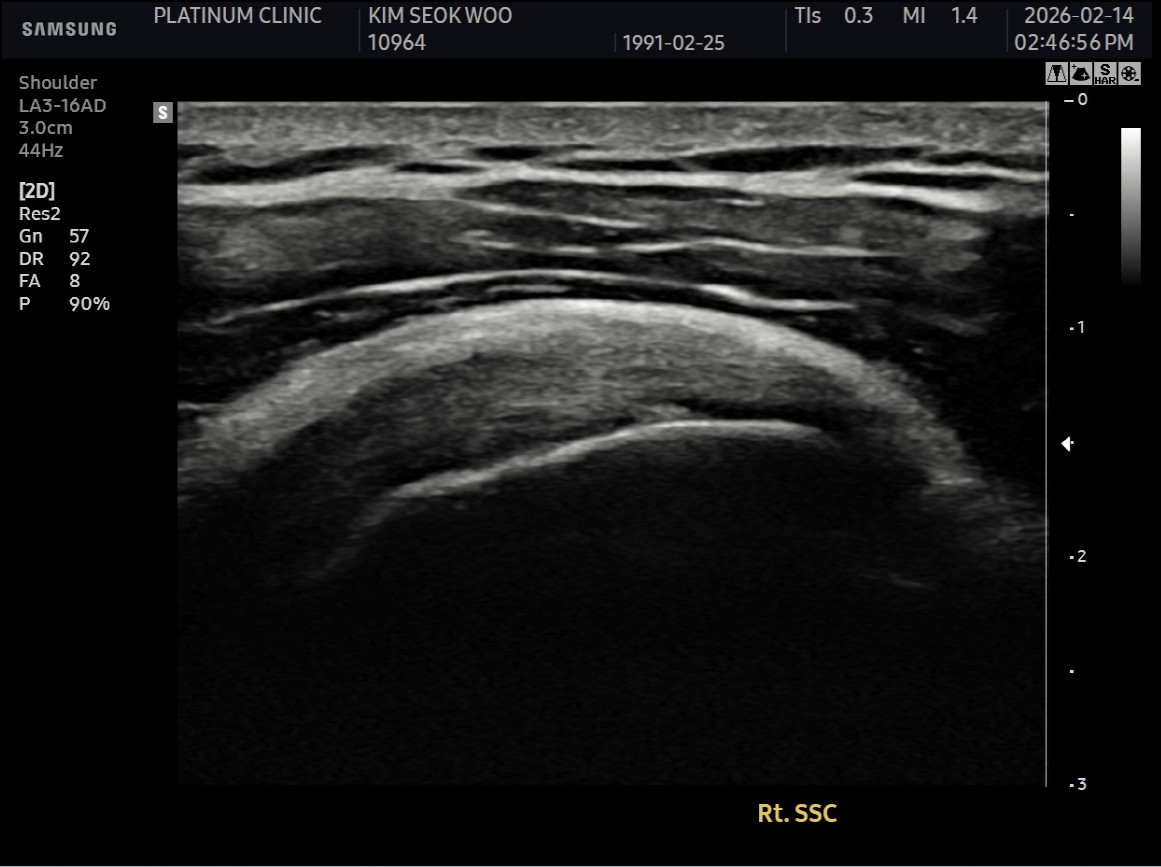

MRI와 초음파 검사 결과:

진단 결과:

- ✓관절면측 부분파열: 약 50%

- ✓점액낭면측 부분파열: 약 35%, 인대 얇아짐 동반

- ✓25년간 반복 사용으로 인한 퇴행성 변화 동반

양쪽 모두 손상된 복합 파열이었습니다.

- ✓관절면측: 봉합 부위 안정적 유지

- ✓점액낭면측: 인대 두께 4.8mm → 6.5mm (1.7mm 증가)